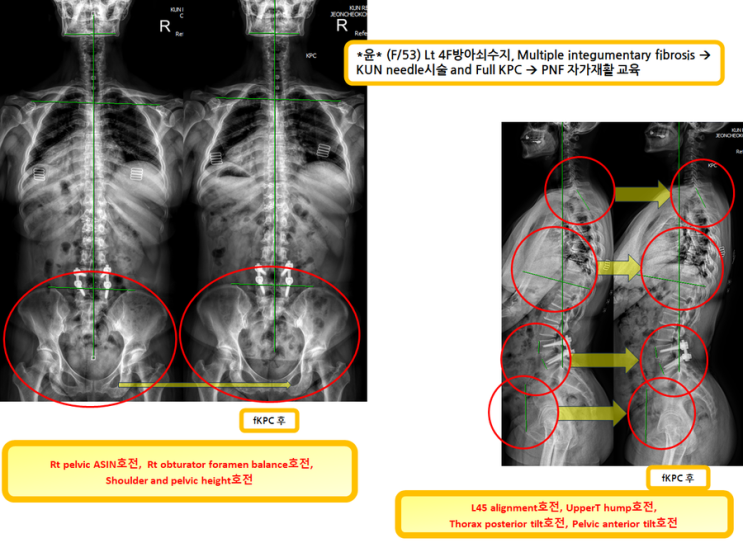

방아쇠수지로 건니들시술하시면서 더불어 full KPC 진행한 분!(녹는실KPC치료는 엑스레이 호전을 10분만에 확인)

방아쇠수지로 건니들시술하시면서 더불어 full KPC 진행한 분! (녹는실KPC치료는 엑스레이 호전을 10...